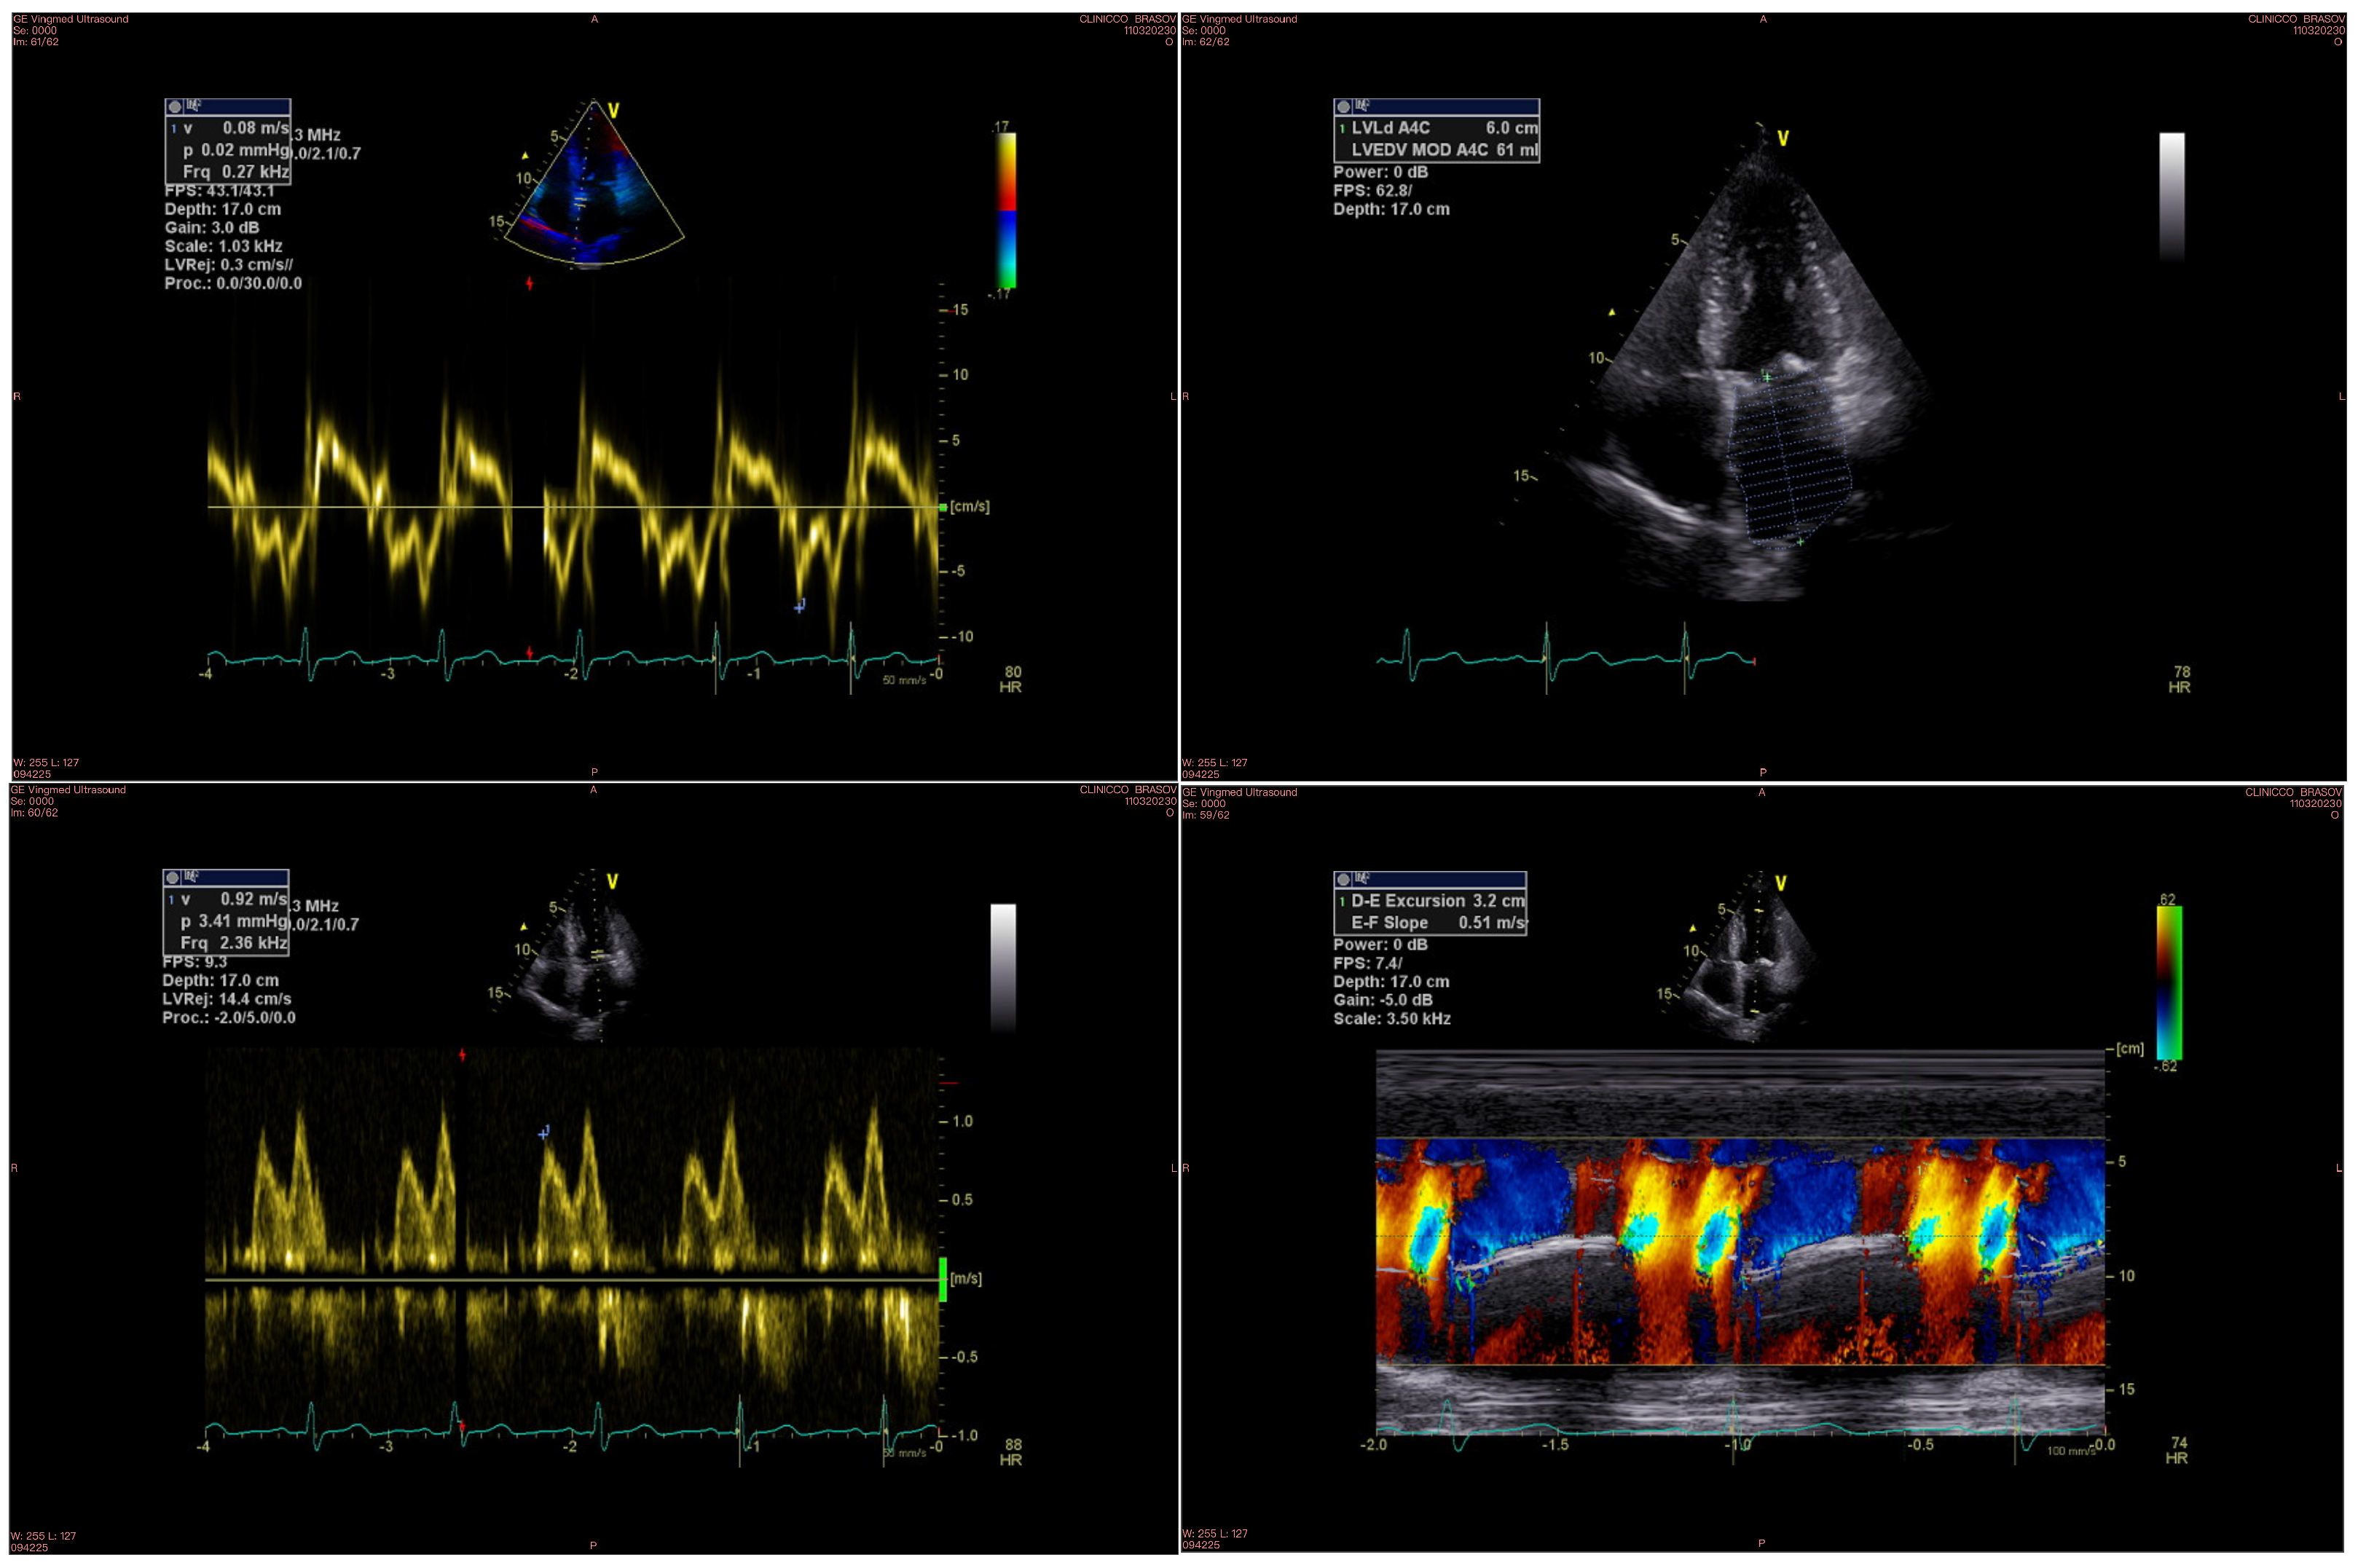

| Parameter | Non-Severe Cirrhosis n = 65 | Severe Cirrhosis n = 37 | p |

|---|---|---|---|

| LV Ejection fraction, mean ± SD [%] | 56.9 ± 6.2 | 58.9 ± 3.9 | 0.06 |

| E/VP, mean ± SD | 1.9 ± 0.3 | 2.2 ± 0.4 | <0.001 |

| Indexed LA volume, mean ± SD [mL/m2] | 30.1 ± 2.9 | 34.5 ± 3.2 | <0.001 |

| E/Em, mean ± SD | 11.5 ± 2.8 | 17.0 ± 3.0 | <0.001 |

| PV, mean ± SD [mm] | 11.5 ± 1.6 | 14.3 ± 2.1 | <0.001 |